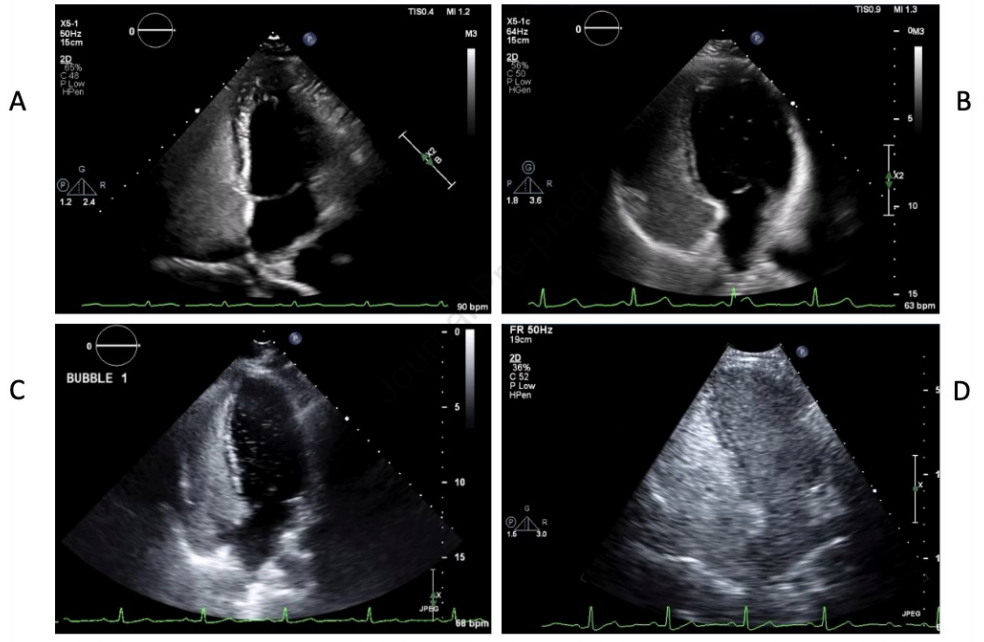

TTCE在检测肺右向左分流方面表现出高敏感性和阴性预测值。现行指南建议阴性者每5-10年复查,但在青春期或妊娠期间应增加监测频率。需要注意的是,高级别分流和已知有大型未治疗PAVMs的病例需要经验丰富的操作者仔细评估,以避免漏掉具有临床意义的分流(图1)。在未确诊HHT的患者中,区分肺内分流和心内分流变得至关重要;肺内分流可通过左心房出现气泡前有四个心动周期的特征性延迟来识别。研究显示约6-25%的正常人群也可能出现右向左分流,这增加了结果判读的难度。不同指南对TTCE在栓塞后监测中的使用建议存在差异,BTS认为其可用于筛查,而HHT国际指南则要求阳性结果必须经CT确认(图2)。

图1.经胸对比超声心动图(TTCE)分级系统。0至3级分别对应:A级(少量,<30个气泡)、B级(中度,30-100个气泡)、C级(大量,>100个气泡),以及左心腔内出现大量气泡混浊伴心内膜轮廓可见的情况。

图2.一名HHT患者的3级TTCE图像。根据麻省总医院HHT方案进行气泡对比剂研究。对比剂级别:3级(大量气泡,>100个)。首次出现的时间是右心显影后3次心跳。激动盐水在3次心跳后早期从右心房到左心房的交叉出现提示可能存在心房间分流,尽管观察到对比剂气泡从肺静脉流出支持肺内分流的判断。分流较大。可见左心显影。